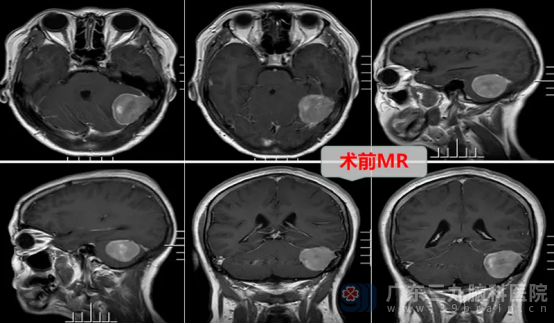

术前,神经外十科团队为患者完善头颅MR和CTA检查,进一步明确了病情。患者的后颅窝左侧枕部-左侧小脑幕下存在占位性病变,范围约40mm×30mm×37mm,考虑脑膜瘤可能性大,且局部与邻近左侧横窦关系密切,病变区还有少许血管影围绕及穿行,这给手术增加了不小的难度。

面对复杂的病情,神经外十科医疗团队进行了充分的术前讨论,制定了周全的手术方案。在一切准备就绪后,神经外十科团队成功为患者行肿瘤切除手术,术中在高清显微镜下全切了肿瘤。